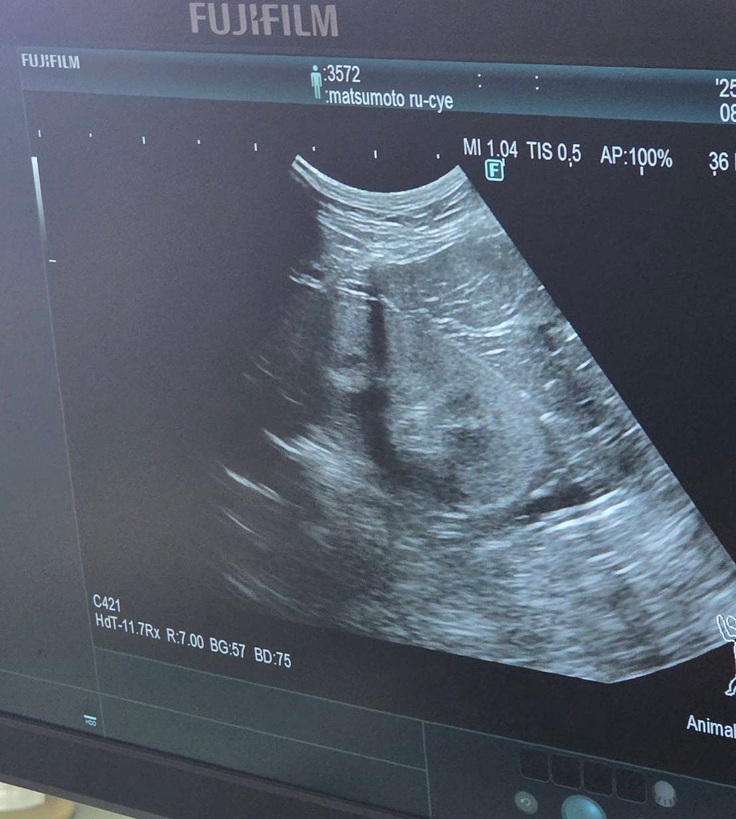

血液検査の写真は撮れなかったのですが、エコー検査では

↓腎臓転移なし

↓肝臓転移なし

↓膀胱転移なし

↓反対側の腎臓も転移なし

↓左目腫瘍なし

↓喉腫瘍なし